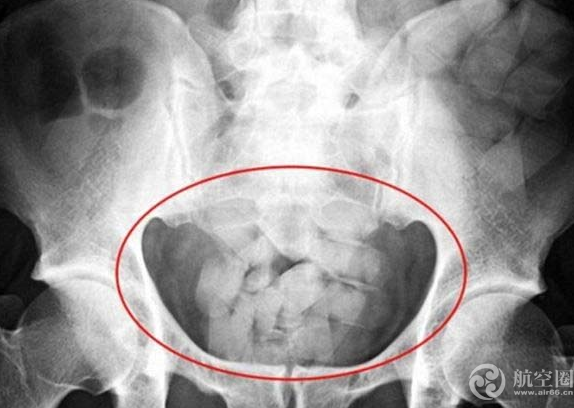

海關(guān)現(xiàn)場工作人員要求其進(jìn)行人體X光機檢查,該旅客卻一直謊稱自己懷孕,拒絕配合檢查。在海關(guān)關(guān)員的一再要求下,海關(guān)關(guān)員對其進(jìn)行了X光機檢查,發(fā)現(xiàn)嫌疑人體內(nèi)藏有毒品可疑物75粒膠囊,凈重956.03克,馬盧卡全部吞入肚中走私入境。

經(jīng)北京市公安司法鑒定中心鑒定,確認(rèn)從犯罪嫌疑人馬盧卡體內(nèi)排出的上述75粒膠囊狀毒品可疑物中的淡黃色粉末為毒品海洛因,含量為23%。